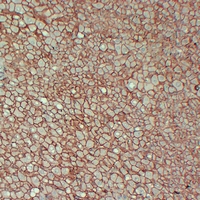

IF (Immunofluorescence)

(Immunohistochemical analysis of Beta-catenin staining in human liver formalin fixed paraffin embedded tissue section. The section was pre-treated using heat mediated antigen retrieval with sodium citrate buffer (pH 6.0). The section was then incubated with the antibody at room temperature and detected using an HRP conjugated compact polymer system. DAB was used as the chromogen. The section was then counterstained with haematoxylin and mounted with DPX.)